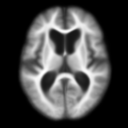

Figure 4 shows the prediction results of our model for one subject sample from the non-demented test group in the OASIS dataset. This subject has MRI scans at 80, 81, 85, and 86 years old, and there are missing images at multiple time points. We predict one image scan per year from 80 years to 88 years, including those missing ones, as shown in the second row of Fig. 4. Since the brain changes are quite subtle (see the first row of Fig. 5), we also plot the deformation map at each time point, as shown in the last row of Fig. 4. These deformation maps show the estimated changes in the brain MRIs. As we can see, the grids are expanding, especially around the brain ventricle region. This expanding ventricle indicates our model captures the degeneration process of the ventricle in the brain, i.e., an enlarging ventricle. Figure 5 shows the image difference between predicted images and their corresponding image scans in the second row. Compared to the first row that shows image difference of follow-up scans with respect to the first one, the prediction difference is relatively smaller, especially around the ventricle region. Table 1 reports the means and standard deviations of the prediction difference for all images in the non-demented and demented groups, which are 5.8616e-41.0703e-4 and 6.1105e-41.9793e-4, respectively.